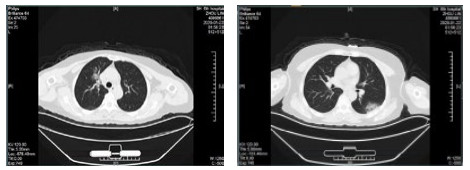

| 图 4 患者,男性,59岁,湖北籍,春节回乡探亲返沪,发热2 d入院,体温37.8℃, 乏力,既往体健。血白细胞总数及淋巴计数正常,甲型、乙型流感筛查阴性,新型冠状病毒核酸检测阳性。肺部CT提示双肺多发磨玻璃结节,病灶贴近胸膜伴支气管充气征及血管充血、增粗,可见部分纤维条索影 Fig 4 Case 4, male, 59 years old, born in Hubei Province, returned to Shanghai during the Spring Festival. He was hospitalized 2 days after fever, with a body temperature of 37.8℃ with fatigue. Normal WBC and lymphoid count, negative influenza A and B virus screening, positive novel coronavirus nucleic acid test. Lung CT showed multiple ground glass nodules in both lungs. The focus was close to the pleura, accompanied by bronchiectasis, hyperemia and thickening of blood vessels. Some fibrous bands could be seen |

| 图 5 患者,女性,44岁,沪籍,发病前10 d内有与确诊NCP患者接触史。出现发热,体温38.5℃,乏力,伴肌肉酸痛,既往体健。血白细胞总数及淋巴计数正常,甲型、乙型流感筛查阴性,新型冠状病毒核酸检测阳性。肺部CT提示双肺多发磨玻璃结节,病灶贴近胸膜伴支气管充气征及病变内血管充血、增粗 Fig 5 Case 5, female, 44 years old, born in Shanghai, had contact history with NCP patients within 10 days before the onset of the disease. Her body temperature was 38.5℃, with fatigue, muscle ache, previous physical fitness. Normal WBC and lymphoid count, negative influenza A and B virus screening, and positive novel coronavirus nucleic acid test. Lung CT showed multiple ground glass nodules in both lungs. The lesions were close to the pleura with bronchiectasis and congestion and thickening of blood vessels in the lesions |